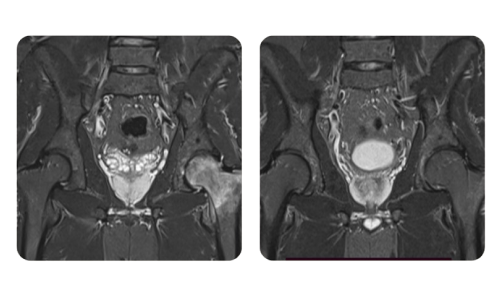

I progressi dei nostri pazienti, misurati prima e dopo la terapia iperbarica, riflettono l'efficacia e l'impatto positivo del trattamento. Scopri i risultati documentati della terapia iperbarica presso la clinica Hyperbarium Oradea, basati su valutazioni cliniche e dati oggettivi che evidenziano miglioramenti significativi in diverse condizioni.